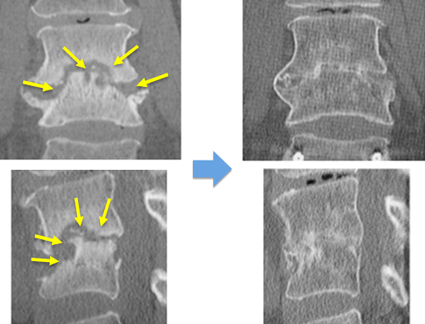

転移性脊椎腫瘍に対する腫瘍脊椎骨全摘術(Total Enbloc Spondylectomy: TES)

脊椎腫瘍では脊椎骨が原発腫瘍やがんの転移腫瘍に占拠された結果、骨を破壊し脊柱の支持性がなくなり局所の痛みを生じます。さらに、腫瘍が脊髄や馬尾神経を圧迫して痛みや神経麻痺を引き起こします場合もあります。その他、脊髄や神経根の圧迫の症状として歩行障害、病的反射、腱反射亢進、膀胱直腸障害、肋間神経痛(胸部痛、しびれ)などが生じます。腫瘍が胸椎にあれば背中からのみで手術を行い、腰椎にあれば周囲の組織を安全に避けるために脇腹からの手術も追加します。

胸椎の腫瘍の場合

背中の皮膚を切開します。摘出する椎体の頭尾側にスクリューを設置し、ロッドで接続して脊椎を強固に固定します。後方より、肋骨を切除し、椎体前面、側面を剥離して、脊髄をよけながら、腫瘍に侵された椎体を一塊として摘出し、同部位に金属性のメッシュに局所骨あるいは腸骨を設置します。

腰椎の腫瘍の場合

まず、横向きの体位としてわき腹を開腹し(正中から開腹する場合もあります)腫瘍に侵された脊椎周囲を十分に剥離を行います。その後、体位をうつぶせに変えて後方より、脊髄をよけながら、腫瘍に侵された椎体を一塊として摘出し、同部位に金属性のメッシュに局所骨あるいは腸骨を設置します。

十分に洗浄し、出血がたまらないようにドレーンと呼ばれる管を留置し、縫合糸をもちいて筋肉と皮膚を創ごとに縫合します。

腎癌の胸椎転移に対するTES手術